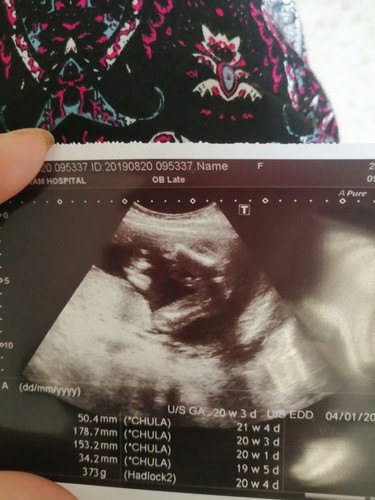

แม่ช่วยดูเพืีอยืนยันหน่อยค่ะ

สวัสดีจร้าแม่ๆทุกคน 20wแล้ว ไปซาวดูแล้ว หมอบอกแม่ว่าได้ผู้ชาย ?แม่ๆว่ามีโอกาศเป็นผู้หญิงได้มั้ยค่ะ??คือแอบเตรียมที่คาดผม ชุดกระโปรงแบบนี้ในเนตไว้แล้วค่ะ คือๆๆแม่อยากทราบว่า100%มั้ยค่ะ????

ผช.มั้งคะเหมือนน้องจะมีไข่ รอดูอีกทีนะคะ แต่มันก็เกือบชัดว่าเป็นผช.นะคะเพราะถ่ายน้องตรงหว่างขาถ้าเห็นไข่ก็เป็นผช.จ้า แต่หนูว่าผช.นะคะเห็นชัดเจนเลย

หน้าจะ ผช นะค่ะ นัองมีจูอยู่ตรงหว่างขา